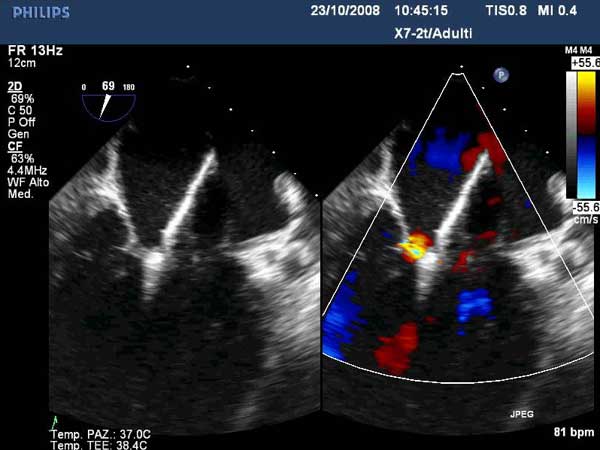

In absence of controlled clinical trial data which are forthcoming from the EVEREST II randomized study, the indications for the MitraClip therapy are currently based on registry experience and will evolve as the technique improves, experience is growing and the data to demonstrate efficacy and safety becomes available. At this time, the best indication for the MitraClip therapy is for symptomatic patients with clinically significant functional or degenerative MR who are at high or increased risk for open heart surgery. From a pure technical standpoint, the procedure so far has only been demonstrated in a subgroup of patients with specific anatomical characteristics which are summarized below and shown in Figure 3. Anatomic suitability is assessed by transesophageal echocardiography, and mitral regurgitation should originate from the central portion of the valve involving the A2-P2 segments, since the device is not ideal to work in the commissures at this time; the mechanism of MR can be either a prolapse/flail or MR due to restricted leaflet motion unrelated to rheumatic disease; the separation between the two leaflets at the site of regurgitation should be limited; severe annular dilatation and/or severe calcification should be absent or is relevant. In case of flail, the flail segment width should be less than 15 mm, and the flail gap less than 10 mm. Figure 4 is a 3D echo image of a patient with posterior leaflet prolapse selected for MitraClip therapy. In case of functional MR, the leaflets should have a minimal residual tissue available for coaptation with the MitraClip device. Figure 5 shows 2D color Doppler jet extension over the coaptation line at TEE short axis transgastric view, while Figure 6 shows the tenting area and the coaptation depth of a patient undergoing MitraClip implant.

3. The Steerable Guide Catheter and Clip Delivery System (CDS) are positioned in the left atrium for clip deployment using echocardiographic and fluoroscopic guidance. The clip arms are opened and the clip is positioned above the origin of the regurgitant jet, with the clip arms perpendicular to the line of coaptation (Figures 12, 13 and 14).

1. Quality of the grasp, valve function and adequacy of repair (reduction of MR) are assessed using echocardiography and fluoroscopy if desired (Figures 16-18). The clip is closed further as needed under real time MR assessment.